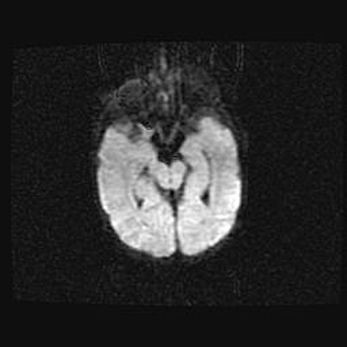

Церебральная ишемия II.

Возраст: 7 дней

Вес: 3350 г

Пол: женский

Окружность головы: 35 см

Срок гестации: 39 недель

Ишемия головного мозга – это состояние, которое развивается в ответ на кислородное голодание вследствие недостаточного мозгового кровообращения. У новорожденных она является следствием дефицита кислорода, что ведет к метаболическим расстройствам различной степени тяжести в тканях головного мозга, в том числе к развитию коагуляционных некрозов и гибели нейронов.